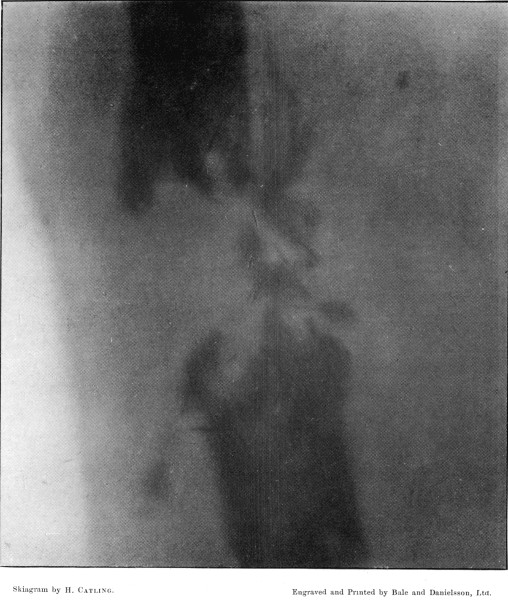

4. Comminuted Fracture of Shaft of Humerus180

5. Comminuted Fracture of Humerus accompanied by an Explosive Exit182